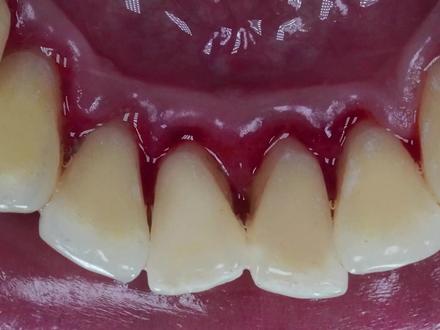

这个小伙实在太懒了,抽了二十多年的香烟都没能养成刷牙的习惯,每次出去相亲,女生看到他这一口大黑牙直呼受不了, 所以小伙只能勉为其难的去洗一次牙齿。只见小伙张开他的血盆大口,映入眼帘的就是一嘴地道的黑色牙结石,就连从业三十年的老牙医看了都佩服不已。牙医将超声波洗牙器塞进小伙的嘴里,在超声波的震动下,一块块细小的牙结石被震动下来。 由于小伙从小就不刷牙,所以牙结石被震下来后,牙齿仍然是黄黄的样子, 看起来就像是玉米粒一般。在牙齿和牙龈的连接处,牙结石就像是老顽固一样,长得十分硕大,奈何碰上了高科技,三下五除二就从扎根了二十年的地方脱落下来。 中间牙齿受灾最为严重,牙医拿着洗牙器不停的滋滋滋,都没能将它扣下来,所以牙医只好换下一颗牙齿操作 表面的黑色菌斑冲洗下来后,一大块牙结石脱落下来,随后立马被吸管吸走,看起来真是太解压了。 没到三分钟的时间,小火口中的牙结石基本都清理干净了,只剩下中间那颗没清理完成的牙齿,看起来是不是很像一个笑脸呢?牙医沿着嘴角处冲洗,顽固的牙结石瞬间四分五裂,明显地方的牙 牙结石清理掉后,牙医又在犄角旮旯的地方完整的清理了一番, 在超声波的作用下,小伙的一口大黑牙被处理的干干净净。看到洗牙前后的明显对比,看来平时不养成良好的刷牙习惯,后果可是让人十分触目惊心的呀!

仔细看这位六十岁的小伙,大门牙正面已经被结石深深的包围,牙齿后面也是漆黑漆黑的,小伙说他每天吃三四包槟榔,吃完一颗槟榔抽一根烟,那种感觉简直快活似神仙,就是有点费牙脱, 你老是打开了心爱的小水枪,水枪所到之处皆是灰飞烟灭,那种酸爽谁起谁知道, 托尼老师一高人胆大,不一会正面的结石就洗不干净,赶紧换到后面,后面的牙齿真的是太黑了,抽烟的朋友应该深有体会。托尼继续表演着他的绝活,黑黑的郊游也在水枪的威力下烟消云散。 一番烧操作,小火牙齿的背面也已经清洗干净, 这样看上去小伙的牙齿是不是非常的漂亮,妥妥的帅哥一枚。